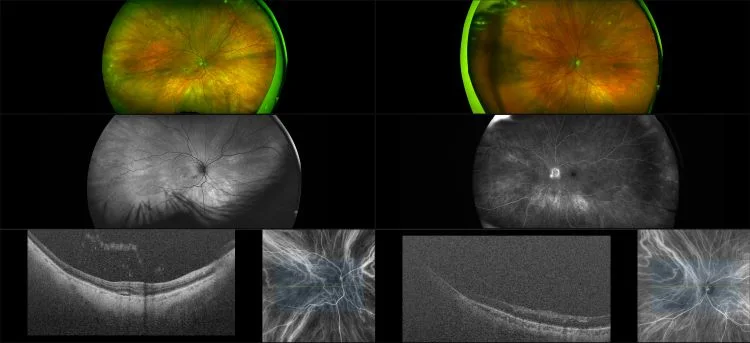

Silverstone - Wet AMD with Sub Retinal Fluid, RG, AF, FA, ICG, OCT

Age-related macular degeneration is found in two forms 1. Dry early form. 2. Wet (serous leakage or whole blood). Early dry form typically has drusen (usually around 63u) and RPE degeneration and only needs periodic follow-ups, intermediate dry form has large drusen (>125u) and RPE degeneration and proliferation which requires examinations every 3 to 6 months depending on the severity of the presentation.